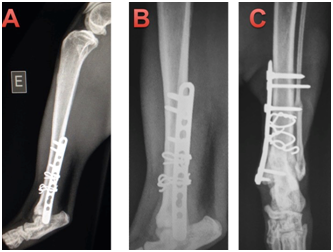

Immediate post-operative radiographs were taken in cat 1 (Figure 3) and 2 (Figure 4), with follow-up radiographs at 21days and 42days post-surgery. The cats were discharged the day after surgery, and re-examined for suture removal after 10days. Cephalexin (30mg/kg every 12hours for 7days orally), meloxicam (0.05mg/kg every 24hours for 3days orally), dipyrone (25mg/kg every 24hours for 5days, orally), tramadol hydrochloride 2mg/kg every 12hours for 5days, orally) were prescribed post-operatively and a protective collar was dispensed to prevent the removal of the stitches. After 10days, the animals returned to HV-UFPR for removal of the stitches and orthopedic evaluation. Immediate post-operative radiographs showed excellent apposition and alignment of bone fragments. Plates were well positioned and fracture lines were not visible (Figure 2). The alignment, fragment fixation, apparatus placement and biological activity were good. The fracture line was not visible, thus showing compression of the fragments using cerclage. The plates have neutral function in both cases, therefore clerk as primary tutor and board as secondary tutor.

Figure 3 Immediate post-operative osteosynthesis of the left tibia of cat 1.

1. Craniocaudal projection in which two cerclage wires were seen to cause compression of the bone fragments (fracture line not visible) and neutral blocked plate, using two screws locked in the distal fragment and three in proximal fragment. Fibular fracture, without implants.

2. Lateral-medial projection showing the same apparatuses as in A, note fracture line not visible.

Figure 4 Immediate post-operative osteosynthesis of the left tibia of cat 2.

1. Mediolateral projection: projection showing two cerclages causing compression of the bone fragments (fracture line not visible) and neutral blocked plate, using two screws locked in distal fragment and three in proximal fragments.

2. Craniocaudal projection showing the same apparatuses as in letter A, again the line of the fracture is not visible, but fracture in the distal fibula can be seen.

Animals were weight bearing at the time of suture removal by 10days the postoperative. On the same day, the limb was examined for weight bearing, palpation at the surgery site, absence of crepitation and instability. At 21days no callus was observed on control radiographs and the implants showed no signs of loosening in both cats. Further radiographs were taken at 42 and 63days, after which time patients were clinically discharged. One of the animals had a four month follow up in the postoperative period and secondary callus was not present in cat 1 or 2, in Figures 5 and 6, respectively. No clinical or orthopedic changes were found after 4months postoperatively (Figure 5) (Figure 6). Some previous studies have postulated that the high incidence of non-union in feline distal tibial fractures is related to a combination of unstable fixation, inadequate blood supply, excessive fracture gaps and interposition of soft tissue between fracture fragments.1 Compression of the fracture line provides continuous bone contact and thus minimizes strain, permitting primary healing.10‒15 Restoration of the bone column by compression of the fracture line also results in rigid stability allowing the weight load to be shared between the bones and implant,10‒13 and decreasing the chances of implant loosening.12

Figure 5 4 months postoperative of the cat 1. In all the images the bone consolidation in tibia has occurred without the production of primary bone callus, showing the total fragmentary compression caused by the cerclage.

1. Mid-lateral radiograph with cerclage wires and blocked plate with neutral function.

2. Close up showing primary bone callus.

3. Craiocaudal projection, showing cerclage.

Figure 6 4 months postoperative of the cat 1. In all the images the bone consolidation in tibia is seen without the production of primary bone callus, showing the total fragmentary compression caused by the cerclage.

1. Crabiocaudal projection showing bone cerclage (compression) and blocked plate with support function. Primary tibial callus is observed in tibia and secondary in tibia.

2. Medio-cranial projection with the same implants as A, showing primary bone callus.